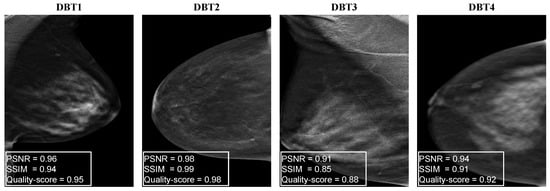

Figure A3 shows the quality scores of the proposed ConvNext-based NR-IQA model with four DBT images. DBT images in Figure A3, DBT1 and DBT4 images suffer from blurring noise and thus obtained the similar quality scores of 0.952 and 0.960, respectively. The DBT image of DBT2 obtained a high image quality score of 0.970 . DBT3 image obtained a low image quality score of 0.810 because bright and dark pixels are diffused over the image.

Figure A3. Quality scores of ConvNext-based NR-IQA model with different DBT images showing different artifacts such as blurring, diminished contrast, and noise manifesting as bright or dark pixels.